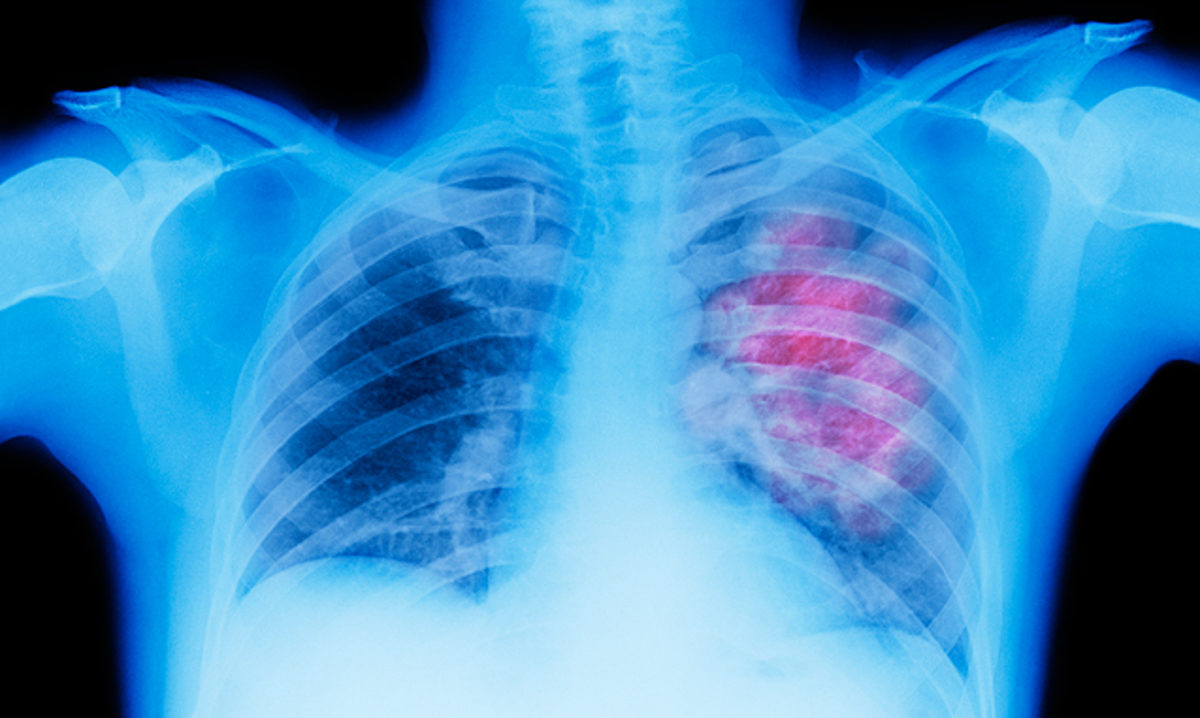

Ο καρκίνος του πνεύμονα, στα αρχικά του στάδια, δεν έχει έντονα συμπτώματα. Μάλιστα, περίπου το 40% των ασθενών που είχαν καρκίνο του πνεύμονα, η διάγνωση έγινε αφότου είχε προχωρήσει αρκετά η ασθένεια.

10: Aξονική τομογραφία

Στα αρχικά του στάδια ο καρκίνος δεν μπορεί να ανακαλυφθεί ακτινογραφία του στήθους. Απο την άλλη, σύμφωνα με μια έρευνα του 2011, οι αξονικές τομογραφίες (CT) scan έχουν αποδεδειγμένα βοηθήσει στη μείωση της θνησιμότητας του καρκίνου του πνεύμονα κατά 20%. Σε αυτή τη μελέτη, 53,454 άνθρωποι με υψηλό κίνδυνο για καρκίνο του πνεύμονα, κάναν αξονική τομογραφία και ακτινογραφία. Οι αξονικές τομογραφίες ήταν πιο αποτελεσματικές στη διάγνωση καρκίνου του πνεύμονα.